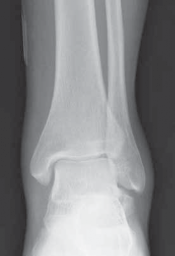

TECHNIQUES B C TECH FIG 1 • A. Bone model highlighting medial intra-articular, lateral extra-articular, and posterior screw fixation. B. Hawkins type II fracture. A C. Postoperative fixation.

The type I fracture is nondisplaced. Disruption of blood flow is limited to the anterolateral region of the bone. I recommend a computed tomography (CT) scan to confirm no displacement of the fracture before diagnosing a type I fracture. Historically, Hawkins reported a 13% incidence of osteonecrosis in type I injuries ( FIG 1A).

In the type II talar neck fracture there is displacement of the talar dome fragment, which is routinely posterior, often depicting clear subluxation of the talar body. Blood flow to the medial body and head is preserved. The type II talar neck fracture has a 20% to 50% risk of avascular necrosis ( FIG 1B). 697

FIG 1 • Hawkins classification of talar fractures. A. Type I: disruption of anterolateral perfusion. B. Type II: medial perfusion intact. C. Type III: all D sources of blood flow injured. D. Type IV: dislocation of all articulations. 1. In the type III injury, the transverse fracture of the talar neck is associated with dislocation of the talar body. The incidence of osteonecrosis of the talar body is 50% to 100%. All major perfusion to the body of the talus is damaged ( FIG 1C). 2. A type IV injury of the talar neck has been documented; it is a type III fracture-dislocation with associated talonavicular dislocation.2 All extraosseous blood flow to the talus is considered disrupted. The value of the Hawkins classification is that it allows the orthopedic surgeon to predict what to expect with a specific talar neck injury. Open reduction and rigid internal fixation is the recommended treatment ( FIG 1D). 1. Talar body fractures are defined as fractures extending into or posterior to the lateral process. PATIENT HISTORY AND PHYSICAL FINDINGS 2. Fractures of the talus are commonly associated with vehicular trauma and falls. 1. The relationship of severe lower extremity trauma and airbags is well known. After airbag deployment, the torso and lower extremities are directed toward the floor panel of the car. 2. I believe that the incidence of high-energy hindfoot trauma will increase over time. Globally, transport related injuries remain the leading cause of disability from injury. By 2020, traffic injuries will increase from a current 9th position to 3rd disability-adjusted life years lost. 3. The history and the clinical status of the talar injury must be carefully recorded because the injury severity is likely to correlate with the long-term patient outcome. 1. On the initial examination the physician should note pain, motion, crepitus, deformity, soft tissue swelling, open fractures, and associated fractures of adjacent bones to the foot and ankle and should perform a complete neurovascular evaluation of the extremity. 4. Detailed documentation of the talus fracture pattern and local soft tissue injury is paramount. 1. Soft tissue local pressure phenomenon, commonly found anterolaterally in closed type III fractures of the talar neck, may precipitate full-thickness pressure necrosis of the skin if not decompressed early. 2. Severe swelling of the ankle is common in the acute fracture of the talus and may progress to fracture blister formation, precluding safe execution of operative incisions. 5. The physician should examine the skin for swelling, ecchy-mosis, fracture blisters, and deformity; these are signs of a closed fracture. 1. A closed injury with mild or moderate swelling (bony landmarks palpable) indicates talar neck type I and II fractures and process fractures. 2. A closed injury with severe swelling indicates talar neck type III and IV fractures and body fractures. 6. Open fractures will be apparent by the transverse, medial, or supramalleolar traumatic laceration of the ankle. Lateral, posterior, and plantar wounds are uncommon. 7. The physician should perform vascular, neurosensory, and myotendinous examinations of the foot and ankle. IMAGING AND OTHER DIAGNOSTIC STUDIES 8. Three plain radiographic views are necessary to radiographi-cally evaluate talus fractures: anteroposterior (AP), mortise (15-degree internal rotation view), and lateral images of the ankle. 1. The AP and mortise views of the ankle demonstrate alignment of the talar body in the ankle mortise. The lateral view depicts the sagittal outline of the talus. 9. The Canale view is used to assess varus or valgus malalignment of the talar neck, particularly with Hawkins type I and II injuries. The knee must be flexed and the foot in equinus and everted, with the x-ray tube directed 15 degrees caudad ( FIG 2A).